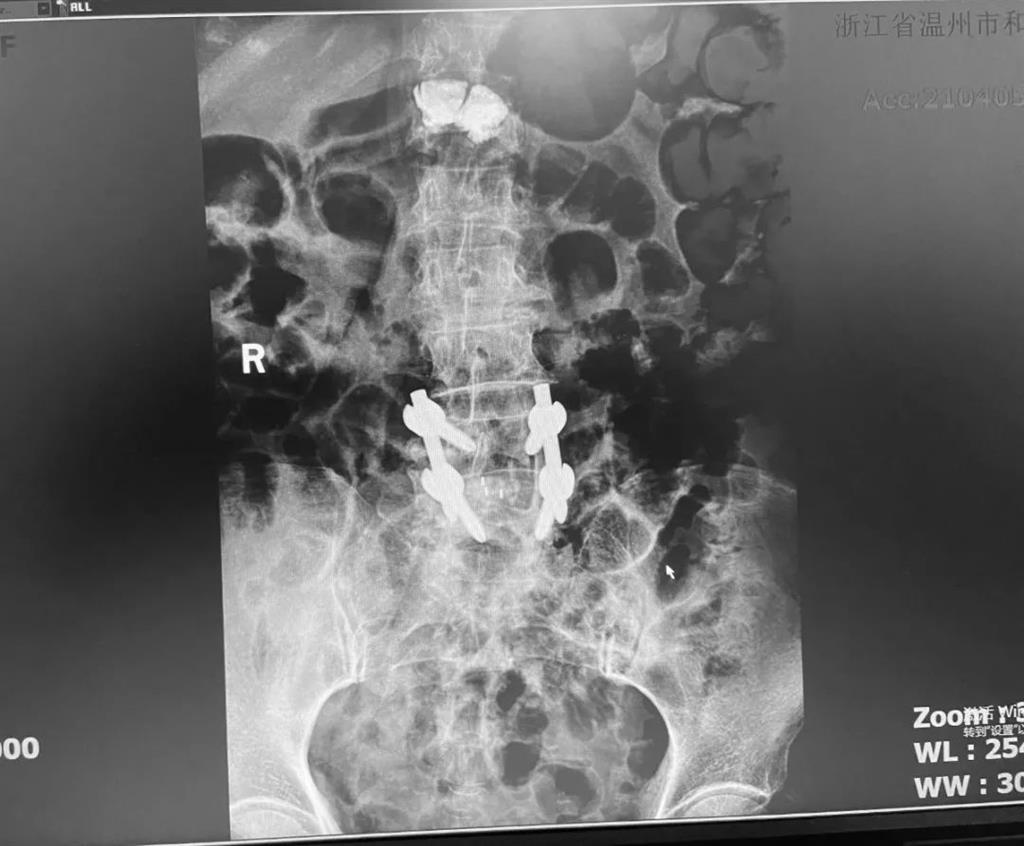

據(jù)了解,脊柱內(nèi)鏡下腰椎融合術(shù)只需要打幾個“鑰匙孔”即可完成。聽起來是不是很簡單?在脊柱內(nèi)鏡下,劉丹主任先后為患者進(jìn)行了椎管減壓、椎間盤摘除,再實施椎弓根螺釘放置、椎體植骨融合內(nèi)固定,一系列步驟有條不紊。

看似簡單的幾個步驟,但實際上很復(fù)雜,需要主刀醫(yī)生有豐富的手術(shù)經(jīng)驗和細(xì)致耐心的操作。

術(shù)中只需切開4個如“鑰匙孔”般大小的孔道